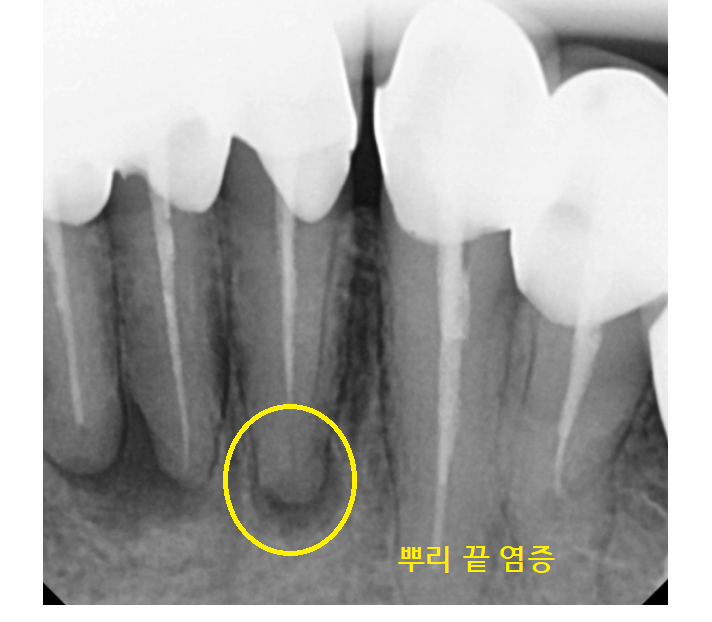

큰 사진에서 의심되는 부분을

추가적으로 검사해 보았더니

어이쿠야..

뿌리 끝에 농양으로

주변 뼈가 녹았네요.